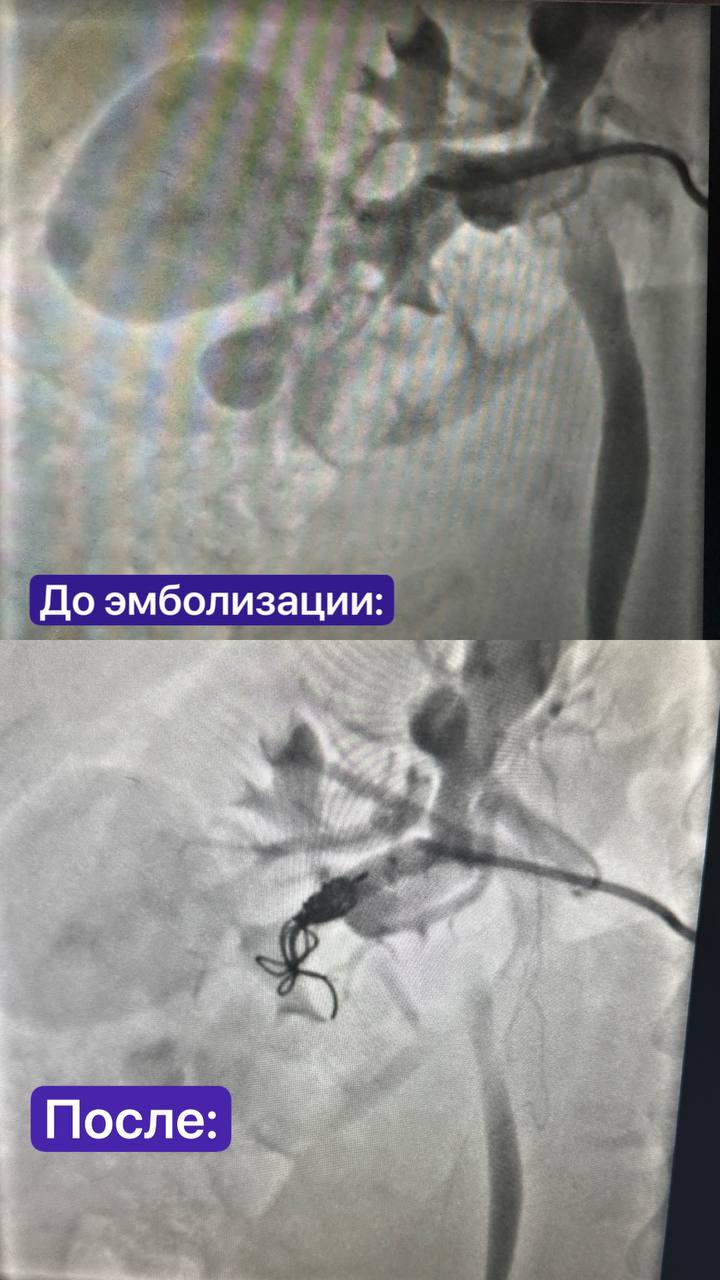

Консилиумда урологлар, хирург-онкологлар, акушер-гинекологлар, балалар реаниматологлары, рентген-хирурглар һәм диагностлар бөер артериясен эмболизацияләү, аннары кесарево кисү һәм шуннан соң бөергә операция ясарга карар кылган.

Йөклелек вакытына карамастан, сабыйның авырлыгы яхшы иде - бу срокта кесарево кисү мөмкин иде. 1 нче номерлы функциональ диагностика бүлеге мөдире Андрей Юрьевич Терегулов артериягә эмболизация ясый, бу икенче аневризма өзелүдән сакланырга һәм шешне «тукланусыз калдырырга» мөмкинлек бирә, ә хирург-онколог Иван Борисович Кутовой һәм уролог Рамил Шамил улы Гыйльметдиновның кансыз методикасы бөерләрне саклап калып, шешне алырга мөмкинлек бирә.